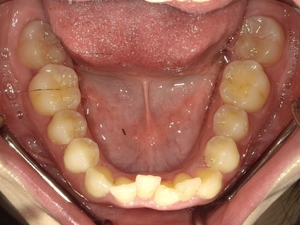

ガタガタとした歯並びや八重歯(叢生)CASE66